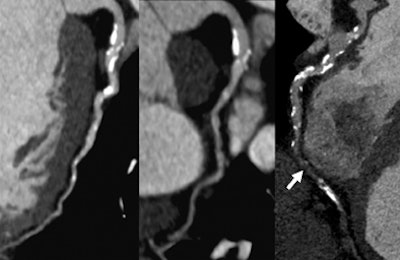

The following paragraphs describe three patients who underwent the comprehensive DSCT protocol along with SPECT myocardial perfusion and MRI for comparison. All images relate to the first patient.

| Images are of a 64-year-old man with a past history of inferolateral myocardial infarction. Rest coronary CT angiography revealed distal right coronary artery occlusion. Functional analysis during systole and diastole showed inferolateral akinesis. First-pass adenosine stress dynamic perfusion CT demonstrated inferior and inferoseptal perfusion defect, confirmed on MRI and SPECT. This perfusion defect corresponds to chronic infarction, as confirmed by delayed-enhancement CT and MRI. Images courtesy of Dr. Gorka Bastarrika, Ph.D. |